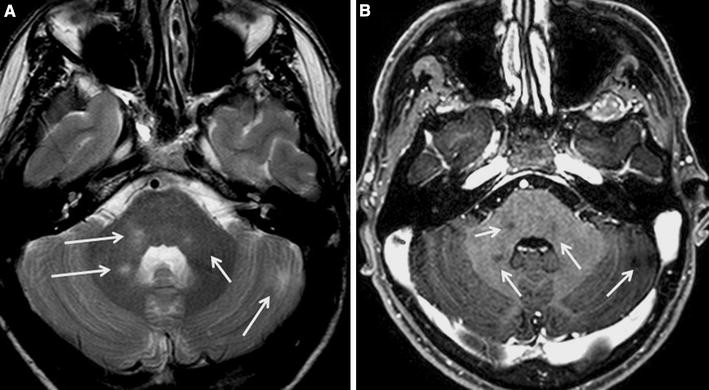

Neuroimage studies